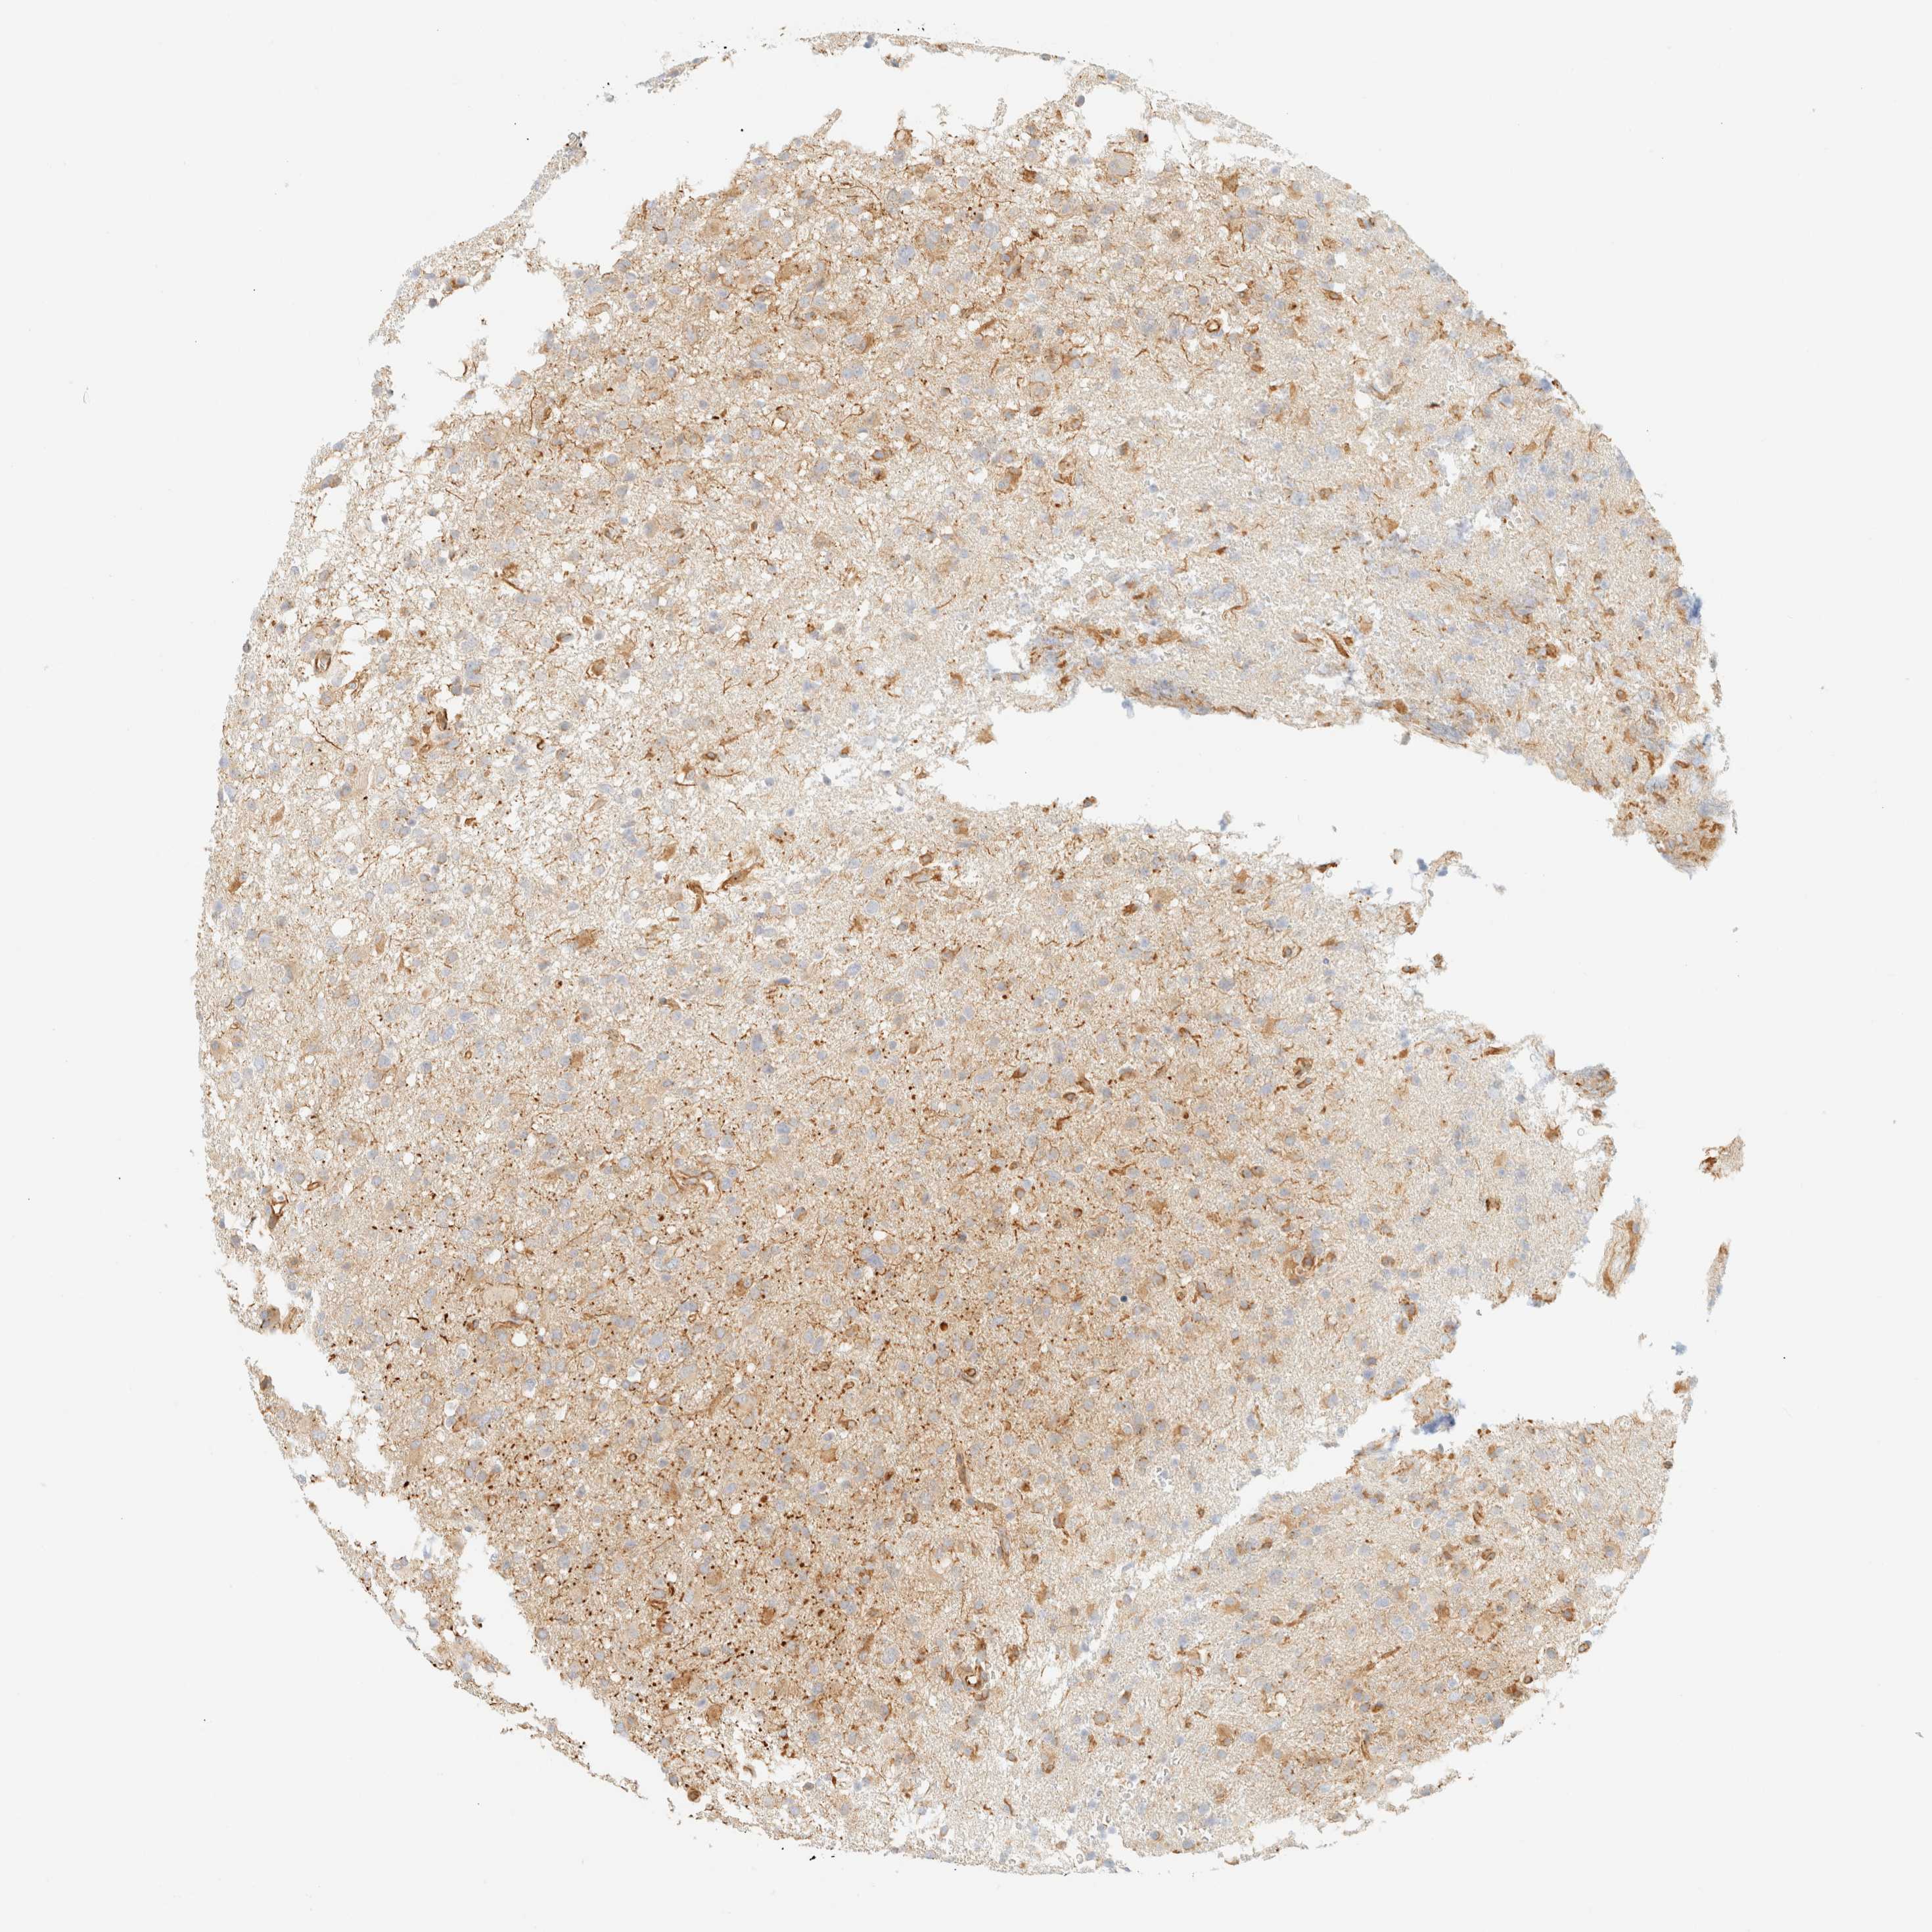

GLIOMA - Protein expressioni

A mouse-over function shows sample information and annotation data. Click on an image to view it in a full screen mode. Samples can be filtered based on level of antibody staining by selecting one or several of the following categories: high, medium, low and not detected. The assay and annotation is described here.

Note that samples used for immunohistochemistry by the Human Protein Atlas do not correspond to samples in the TCGA dataset.

Antibody stainingi

Antibody staining in the annotated cell types in the current human tissue is reported as not detected, low, medium, or high, based on conventional immunohistochemistry profiling in selected tissues. This score is based on the combination of the staining intensity and fraction of stained cells.

Each image is clickable and will lead to virtual microscopy that enables deeper exploration of all samples and also displays staining intensity scores, fraction scores and subcellular localization as well as patient and tissue information for each sample.

Antibody HPA024524

Antibody HPA053090

Staining

High

Medium

Low

Not detected

Intensity

Strong

Moderate

Weak

Negative

Quantity

>75%

75%-25%

<25%

None

Location

Nuclear

Cytoplasmic/membranous

Cytoplasmic/membranous,nuclear

Glioma, malignant, High grade

Glioma, malignant, Low grade